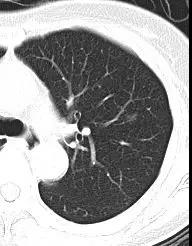

這些小結(jié)節(jié)長度通常在2厘米以下,其中大部分在CT片上呈現(xiàn)為“磨玻璃”樣模糊的小腫塊,因此醫(yī)學(xué)上將其稱為磨玻璃樣病變(英文“Ground Glass Opacity”,簡稱GGO),并非真的玻璃。

肺部磨玻璃樣變結(jié)節(jié)在CT影像下